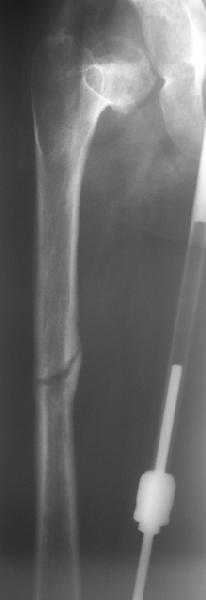

Поступила к нам в отделение. В отделении первым этапом был наложен аппарат внешней фиксации для низведения бедра. 30.09.08 интрамедуллярный стержень удален. Вторым этапом планируется эндопротезирование. В настоящее время у больной имеется контрактура коленного сустава, с амплитудой движений в пределах 30 градусов., и выраженный остеопороз вертлужной впадины и проксимального отдела бедра. Больныя пердвигается самостоятельно с опорой на здоровую ногу и костыли.

Какие проблемы при эндопротезиовании в этих условиях ожидать, и как с ними бороться? Еще и диафиз сросся не очень крепко, опасаемся, как бы не сломать. Очень выражен местный остеопороз, может быть, сделать все-таки цементный протез? Хотя 18 лет всего. Спасибо.